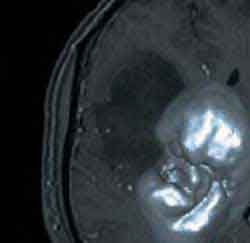

3D-модели раковых опухолей позволяют лучше понять причины рака

3D-принтеры можно использовать в сочетании со сканами системы автоматизированного проектирования для распечатывания клона опухоли перед операцией, с тем чтобы хирурги точно знали, с чем именно им придется иметь дело и могли подготовиться к операции, "порепетировать" её ход на пластиковой модели. 3D-модели также используются для изучения процессов развития раковой опухоли: ученые из Техасского университета полагают, что к раку приводит механическая деформация клеток. Для доказательства своей теории они построили 3D-модель развития раковой опухоли, в которой был продемонстрирован процесс изменения связей между клетками, в результате чего те начинали бесконтрольно делиться и образовывать опухоль.